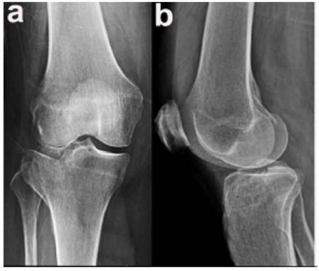

Um paciente de 39 anos de idade, vítima de queda de bicicleta, sofreu trauma no joelho direito. Foi levado ao pronto-socorro do hospital mais próximo, onde foram realizadas as radiografias apresentadas.

Um paciente de 39 anos de idade, vítima de queda de bicicleta, sofreu trauma no joelho direito. Foi levado ao pronto-socorro do hospital mais próximo, onde foram realizadas as radiografias apresentadas.

Um paciente de 39 anos de idade, vítima de queda de bicicleta, sofreu trauma no joelho direito. Foi levado ao pronto-socorro do hospital mais próximo, onde foram realizadas as radiografias apresentadas.

Um paciente de 39 anos de idade, vítima de queda de bicicleta, sofreu trauma no joelho direito. Foi levado ao pronto-socorro do hospital mais próximo, onde foram realizadas as radiografias apresentadas.